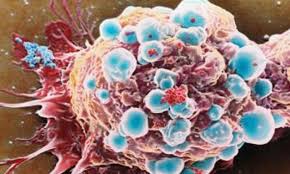

Cosa sono le sindromi linfoproliferative Le patologie linfoproliferative sono un gruppo secondario di patologie che interessano gli organi linfoidi secondari; il primo gruppo sono i linfomi Hodgkin e Non-Hodgkin. Principali sindromi linfoproliferative Le principali...

Che cos’è la leucemia acuta Le leucemie sono un gruppo eterogeneo di neoplasie che originano dalla trasformazione neoplastica di cellule emopoietiche. La cellula bersaglio della trasformazione leucemica può essere rappresentata dalla cellula staminale pluripotente...

Le emergenze oncologiche sono situazioni critiche per la vita del paziente, determinate dalla malattia e/o dal trattamento antineoplastico. Le più importanti sono: emergenze neurologiche. emergenze metaboliche. emergenze ematologiche. sindrome della vena cava superiore. ...